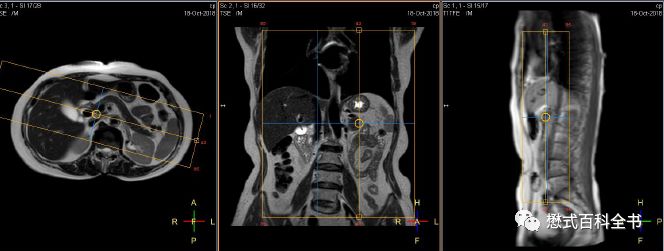

图17:MRCP的定位

如果单独扫描MRCP,我们除了扫描定位像,首先需要扫描一个冠状位的T2WI好作为参考。最好再推荐扫描一个T2脂肪抑制的横轴位,这样MRCP的定位就更准确了。

定位的时候,在冠状位和横轴位上面一起定MRCP扫描的角度。